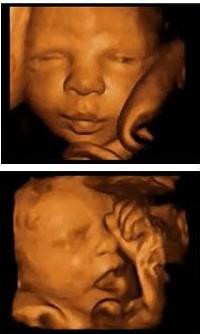

四维彩超就是采用三维超声图像加上时间维度参数。该革命性的技术能够实时获取三维图像,超越了传统超声的限制,更清晰,能够多方位、多角度地观察宫内胎儿的生长发育情况,为早期诊断胎儿先天性体表畸形和先天性心脏疾病提供准确的科学依据,可从多方位为孩子拍照,也可为胎儿做写真集,更具特殊意义。

四维彩超表面成像用于产科检查,不仅可观察到胎儿成长的过程,而且能够直观地看到胎儿在母体内的活动状况,如:呼吸情况,运动情况,包括整个身体大的运动,肢体的运动,甚至是胎儿细小的吞咽动作等。医生还可以通过四维彩超来观察胎儿的张力是否良好。